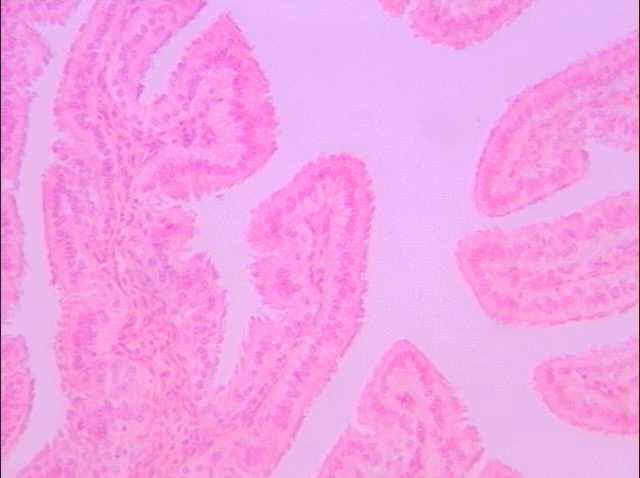

切片位置:輸卵管(oviduct)

切片倍率:100x

染色方式:h&e stain

此為輸卵管組織之橫切,可見輸卵管組織向內突出之縱向皺褶構造,縱向皺褶包含上皮組織及其下方之結締組織,輸卵管上皮為單層柱狀纖毛上皮。